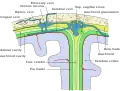

Contrairement aux feuillets plus externes (arachnoïde et dure-mère) qui suivent l’endocrâne, la pie-mère dans sa partie cranienne épouse étroitement le relief du parenchyme en suivant les sillons, scissures et circonvolutions du cortex cérébral, ce qui fait que sa surface est beaucoup plus importante que celles des autres méninges qui sont tendues au-dessus des renfoncements du tissu nerveux. Les espaces ainsi formés entre la pie-mère et l’arachnoïde sont appelés espaces sous-arachnoïdiens ; certains sont plus largement dilatés en ce qu’on appelle des citernes sous-arachnoïdiennes, elles sont situées à la base du crâne principalement autour du tronc cérébral. Les espaces sous-arachnoïdiens sont remplis de liquide cérébrospinal anciennement appelé liquide céphalo-rachidien (LCR) et traversés par des trabéculations ou travées arachnoïdiennes qui attachent la pie-mère à la face interne de la membrane arachnoïde.

Coupe sagittale médiane du cerveau. Coupe coronale de la branche inférieure (corne temporale) d'un ventricule latéral.

Coupe coronale de la branche inférieure (corne temporale) d'un ventricule latéral. Représentation schématique d'une coupe du haut du crâne, montrant les membranes du cerveau.